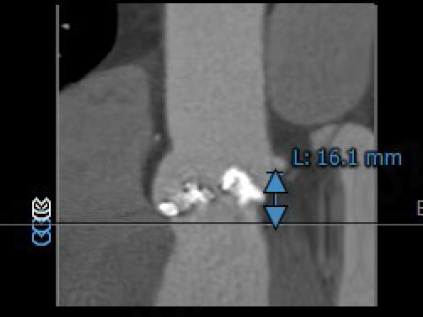

左冠开口高度:16.1mm

右冠开口高度:16.1mm